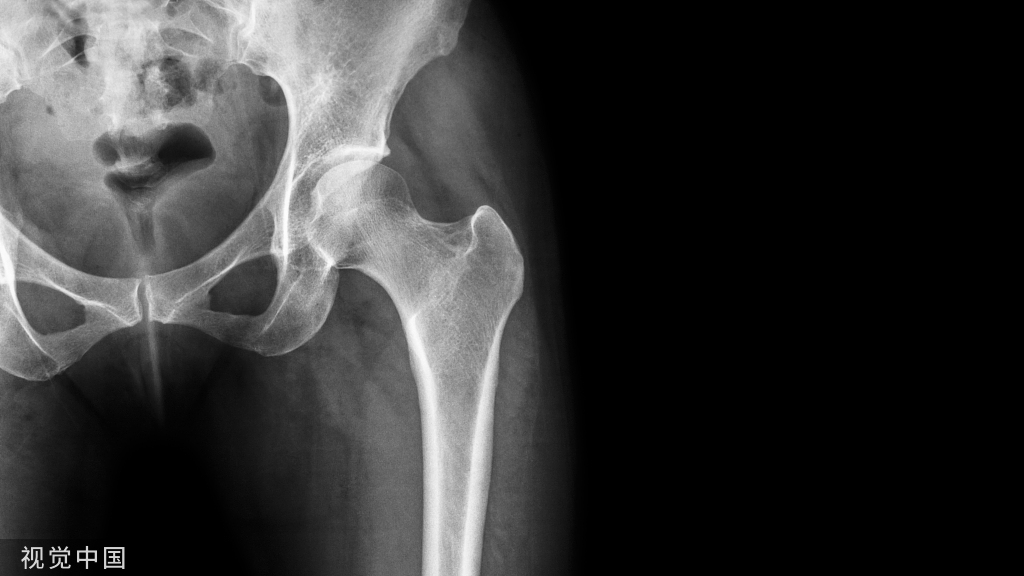

用于目标肢体延长的关节炎严重程度分级。(A)关节间隙轻度变窄的目标是延长2-3 mm。(B)完全缩小关节间隙的目标是加长4-5mm。(C)股骨头扁平或髋臼骨质侵蚀可延长5~6mm。(D)股骨头和髋臼侵蚀的目标是延长6mm或更长。